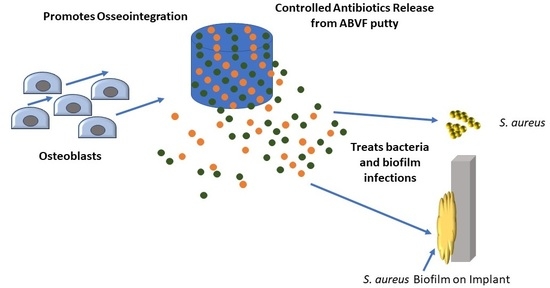

:1. Introduction

2. Materials and Methods

2.3.1. Preparation of ABVF

4. Discussion

5. Conclusions